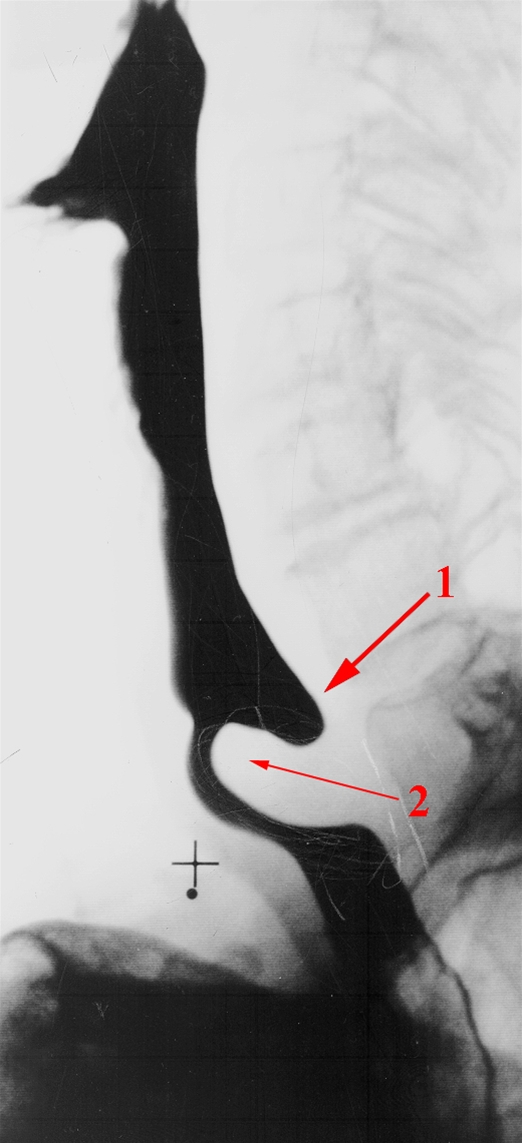

Figuren er en røntgen kontrastoptagelse af øsofagus (spiserøret)

1. Udposning bagtil i nedre del af spiserøret

2. Udposningen skyldes en svækkelse i spiserørsmuskulaturen